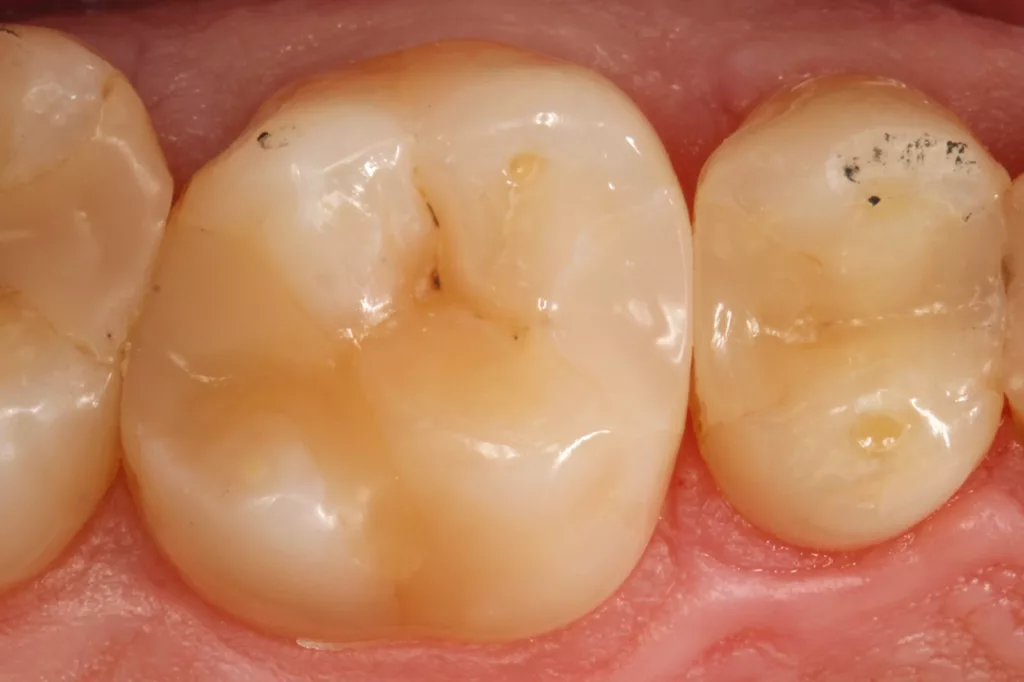

Fall 5: Versorgung einer okklusalen Kavität an einem unteren Molaren

Auch im Molarenbereich können Bulkflow-Materialien effektiv und ökonomisch eingesetzt werden, ohne Abstriche an der Ästhetik machen zu müssen, was der Fall des hier versorgten Zahnes 46 bei einer 22-jährigen Patientin zeigt. Die Abbildung 24 stellt die bereits präparierte und mit einem Einzelzahnkofferdam isolierte Kavität mit der Phosphorsäurekonditionierung der Schmelzränder (Gel Etchant, Kerr) dar. Die Entscheidung zur absoluten Trockenlegung fiel aufgrund der nicht so einfach kontrollierbaren Zunge und der vielen Schluckreflexe, was das Risiko einer ungewollten Speichelkontamination der Klebefläche unverhältnismäßig erhöhte.

Die Verwendung des Kofferdams ist generell eine sehr empfehlenswerte, aber keine zwingende Voraussetzung zur Etablierung einer suffizienten Kontaminationskontrolle [47,96]. Das bisher auch bereits verwendete Zwei-Schritt-Universaladhäsiv G2 Universal wurde hier in der selektiven Schmelzätztechnik angewendet, d.h., das Material arbeitet auf dem Dentin selbstkonditionierend (Abb. 25). Die bislang zu diesem innovativen Mehrflaschen-Universaladhäsiv publizierten Daten zeigen eine beeindruckende Performance, die den Vergleich mit sogenannten Goldstandards [98] wie einem Optibond FL nicht scheuen müssen [13,18,34,58,63,114,119,127,130]. Im nächsten Schritt wurden die einzelnen Höcker mit dem angenehm standfesten Flowable aufgebaut (Abb. 26). Die Abbildung 27 zeigt die komplett versorgte okklusale Kavität, die Abbildung 28 die Situation unmittelbar nach Ausarbeitung und Politur. Erneut beeindruckt die gute Farbadaptation.